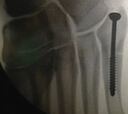

Dr. Ripoll: "Xabi es como Rafa Nadal y en 45 ó 60 días correrá"

Xabi Alonso, operado en Murcia

Una lesión inoportuna por su edad